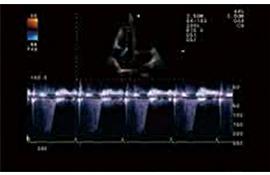

TDI組織多普勒成像

TDI已成為重要的心臟功能評估技術(shù),能夠精確分析高幅、低頻多譜勒頻移及通過彩色編碼實時顯示心肌組織的運動速度。TDI能夠無創(chuàng)診斷心肌收縮、舒張的速度,進行左室收縮、舒張功能的評價,特別在舒張功能的評價方面,TDI能夠在收縮功能受累之前的心肌運動低下的病人得到早期的診斷,并得出沿室壁內(nèi)膜運動的速度,用以評價左室節(jié)段運動的狀態(tài),獲得高質(zhì)量的多譜勒信息,測出速度、平均速度和瞬間加速度等參數(shù)值。此項技術(shù)為臨床冠心病、心肌病、心律失常等多種疾病的診斷提供了可靠的診斷依據(jù)。

組織多普勒成像TDI是常規(guī)檢查必不可少的工具,用于評估心臟舒張功能。Xario200TDI 頻譜自動包絡(luò)功能具有很高的靈敏度。

自由M型(Flex-M):可對傳統(tǒng)M型進行解剖修正,可實時完成或在存儲的二維圖像上進行,與常規(guī)M型有著相同的質(zhì)量和功能。